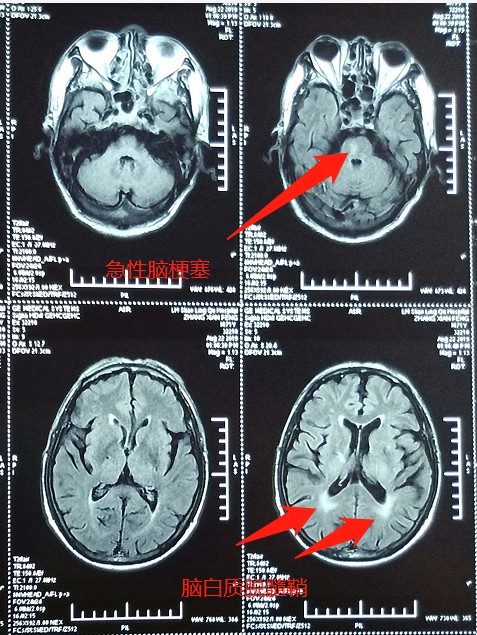

核磁共振可见急性脑梗死。